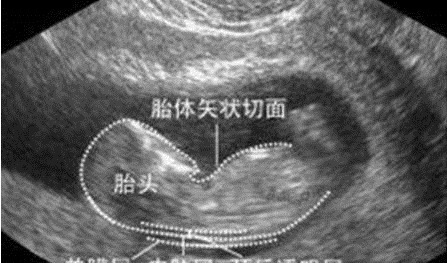

1)早唐+NT在孕期11~14周之间做的检查,早唐+NT其实是两项不同的检查,早唐是抽血检查,而NT是B超检查,之所以合并在一起,是因为检查的时间非常相近。早唐检查的准确率是远高于中唐筛查的,但因为NT检查对医生技术、设备精度的要求都非常高,因此并不是每个医院都支持早唐+NT的检查,需要孕妈自己预约去检查。▼ 需要注意:这次检查一定要在孕期14周前完成,否则胎儿颈部透明带消失,就无法进行检查了。

孕妈在NT检查前可以带一些食物,因为NT检查需要胎儿呈现特定的姿势才能看清,在检查中适当进食,可以促进胎儿移动,帮助调整最佳的姿势。2)中唐筛查中期唐筛几乎是每个医院必检查的项目,一般在孕期的14~20周进行,最佳的检查时间是孕期18周。虽然中唐检查的准确率不高,但却也是非常重要的参考,检查的结果一般分为三个:1/270以上,高风险;1/1000~1/270,中风险;1/1000以下,低风险。